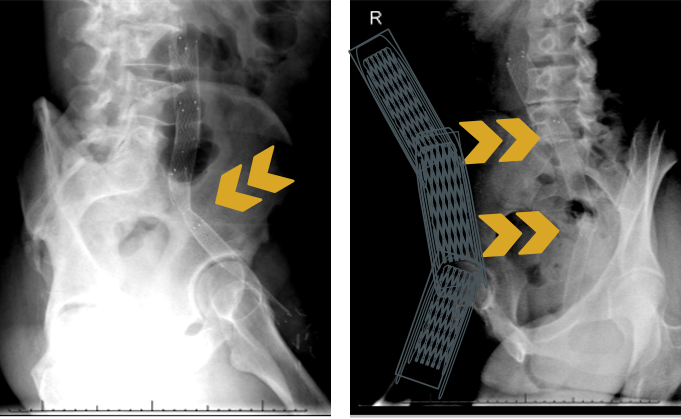

术后:支架定位困难,未能完全覆盖病变

图:术后

★ 定位困难,长度不可控

释放过程中支架定位不精准,无法精确控制其突入上腔静脉或下腔静脉的长度,这是现有器材的局限性,可能导致并发症或影响未来治疗选项。